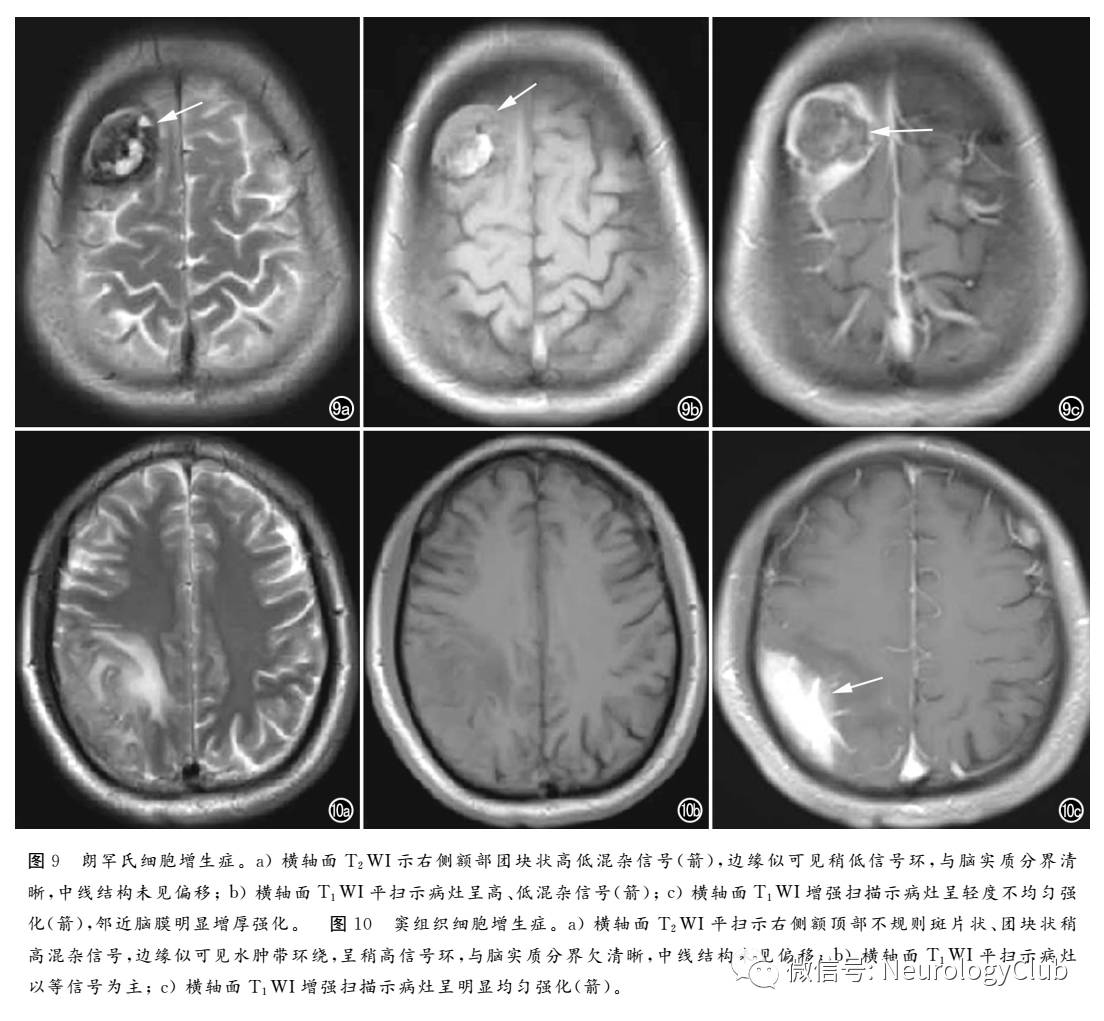

朗罕氏细胞增生症(Langerhans’cell histiocytosis,LCH)是一种以朗罕氏细胞在一个或多个器官增生为特点的疾病,临床上分为三型:①单系统、单病灶(嗜酸性肉芽肿)(图9);②单系统、多病灶(Hand-Schuller-Christian病);③多系统、多病灶(Letterer-Siwe病)

窦组织细胞增生症(Rosai-Dorfman病)是一种罕见的良性组织细胞增生性疾病,病理学上表现为不同形态的组织细胞、大量成熟的浆细胞和淋巴细胞组成“明暗”相间的区域。中枢神经系统结外Rosai-Dorfman病病变主要位于大脑凸面、矢状面、鞍上、海绵窦和岩骨斜坡区。超过90%的病变附着于脑膜,病变范围常较大,T1WI多表现为等信号,T2WI为不均匀等或低信号,增强扫描呈明显均匀强化,病变周围多伴中至重度水(图10)。